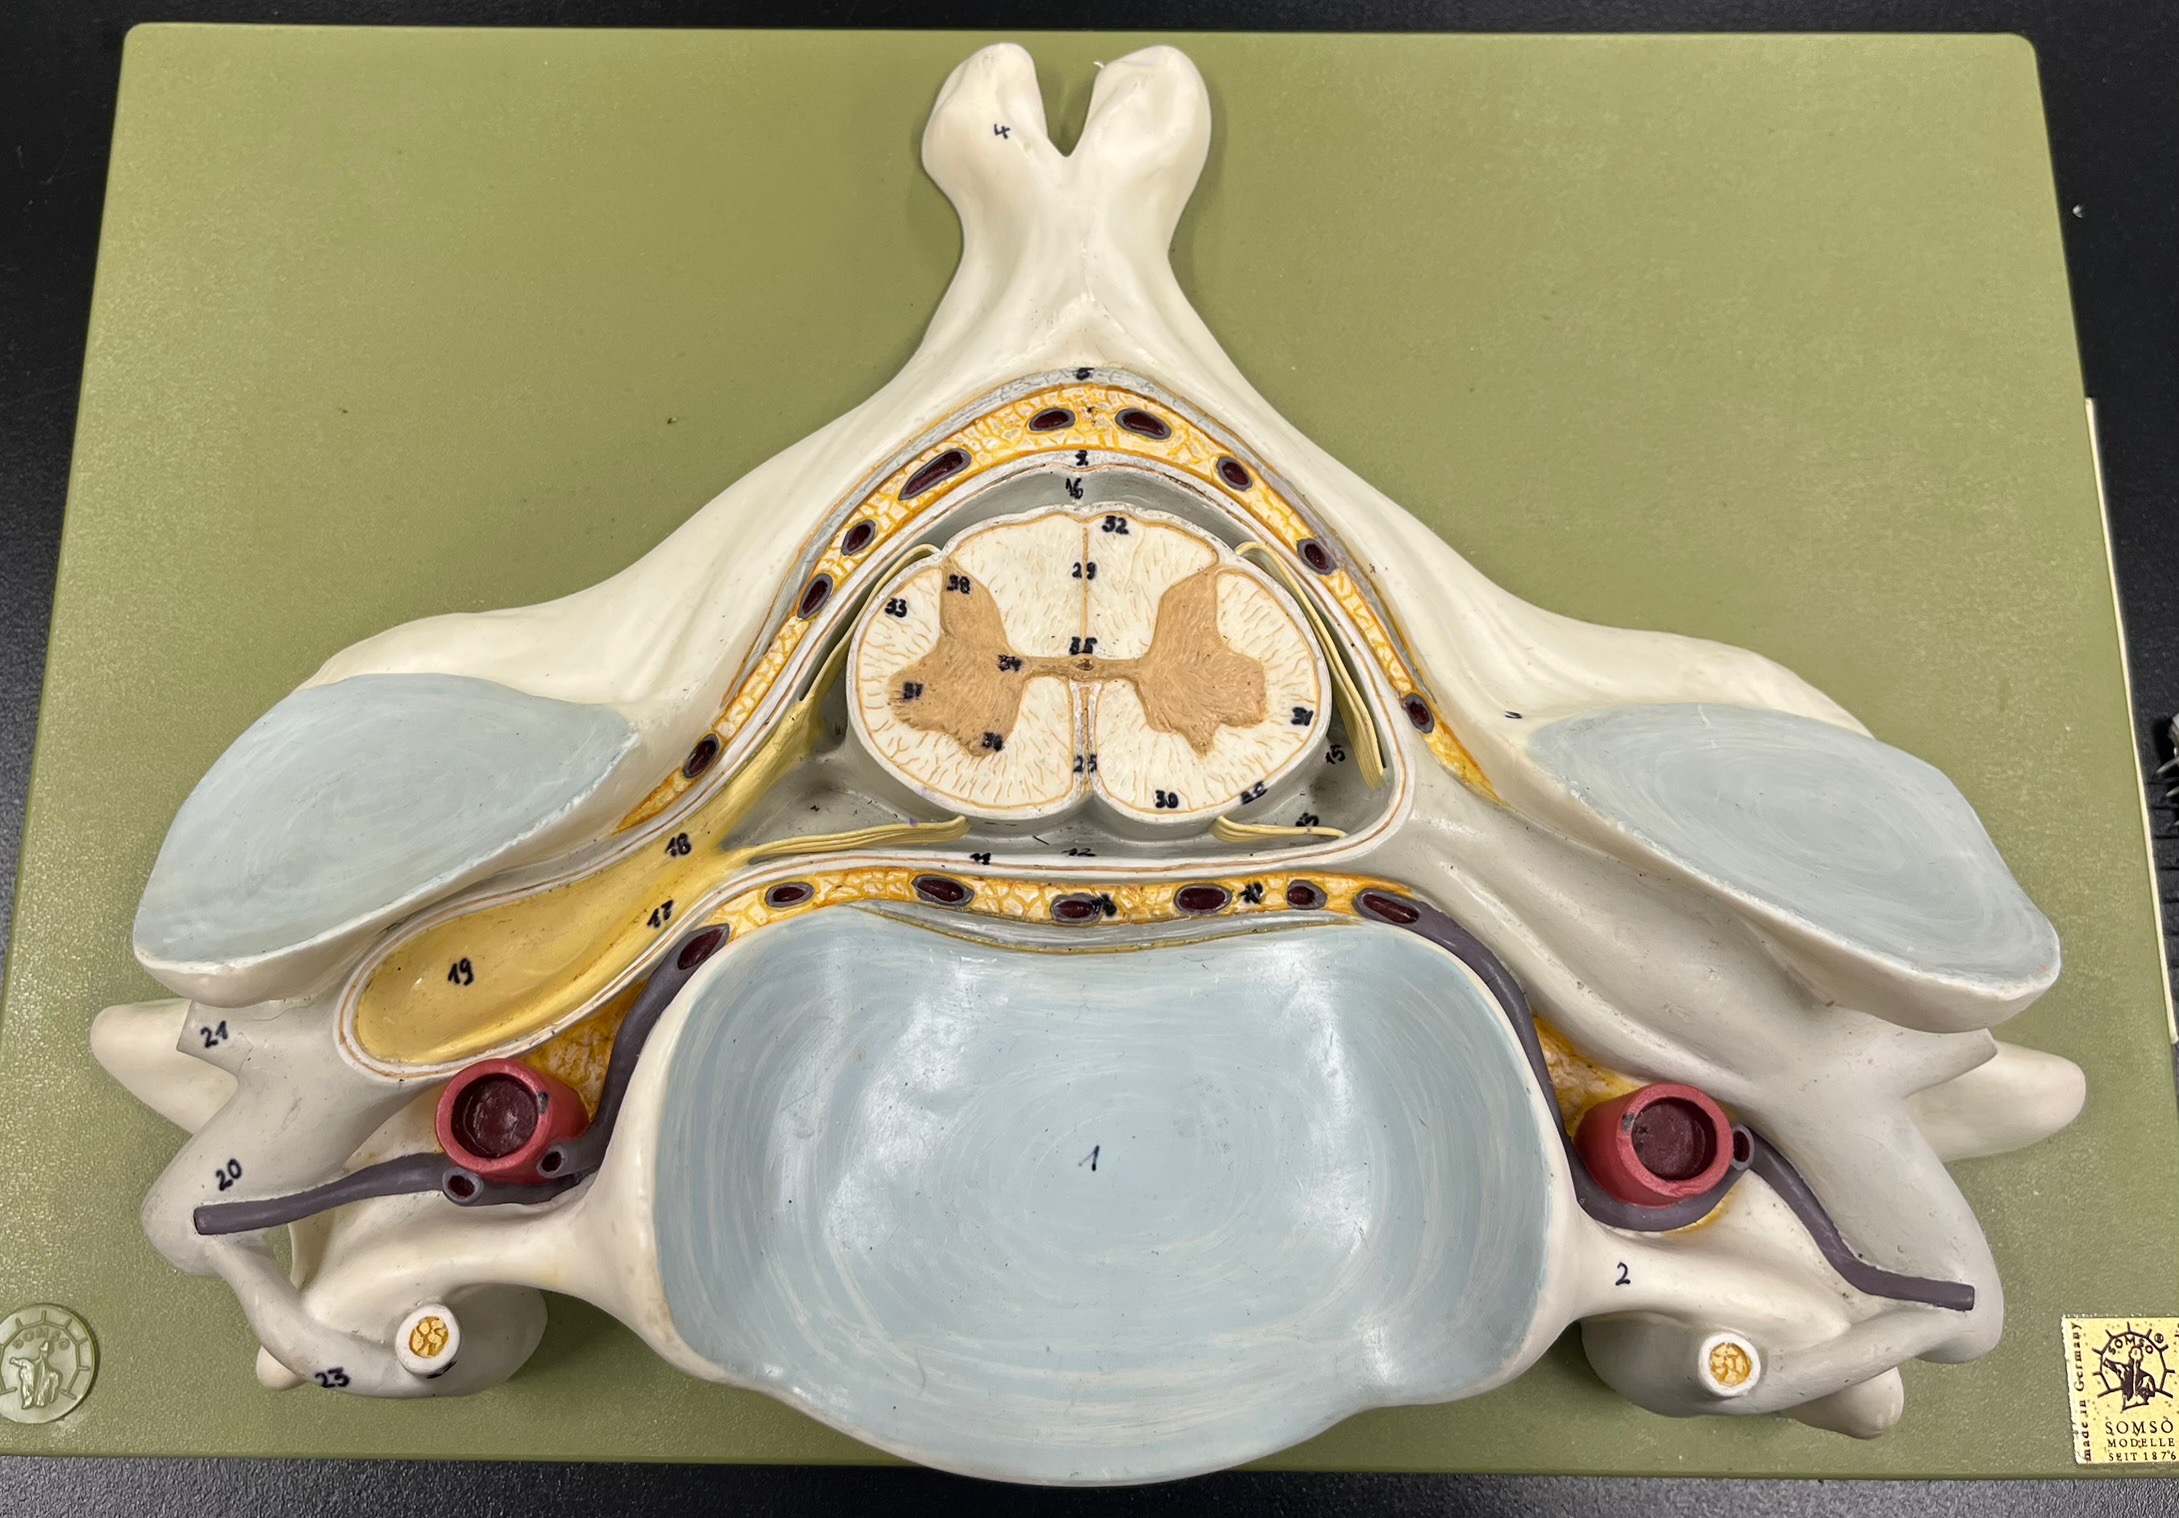

epidural space

dura mater

subdural space

arachnoid mater

subarachnoid space

pia mater

denticulate ligaments

What is the groove here?

anterior median fissure

posterior median sulcus

posterior (dorsal) horn

posterior (dorsal) horn; R—>L

anterior (ventral) horn

lateral horn (selected models)

gray commissure

central canal

anterior column

lateral column

posterior column

white commissure

posterior (dorsal) root ganglion

What is the bulb here?

posterior (dorsal) root ganglion

posterior (dorsal) root

posterior (dorsal) root

anterior (ventral) root

anterior (ventral) root

dorsal ramus

dorsal ramus

ventral ramus

ventral ramus

rami communicantes

rami communicantes

sympathetic chain ganglia

sympathetic chain ganglia